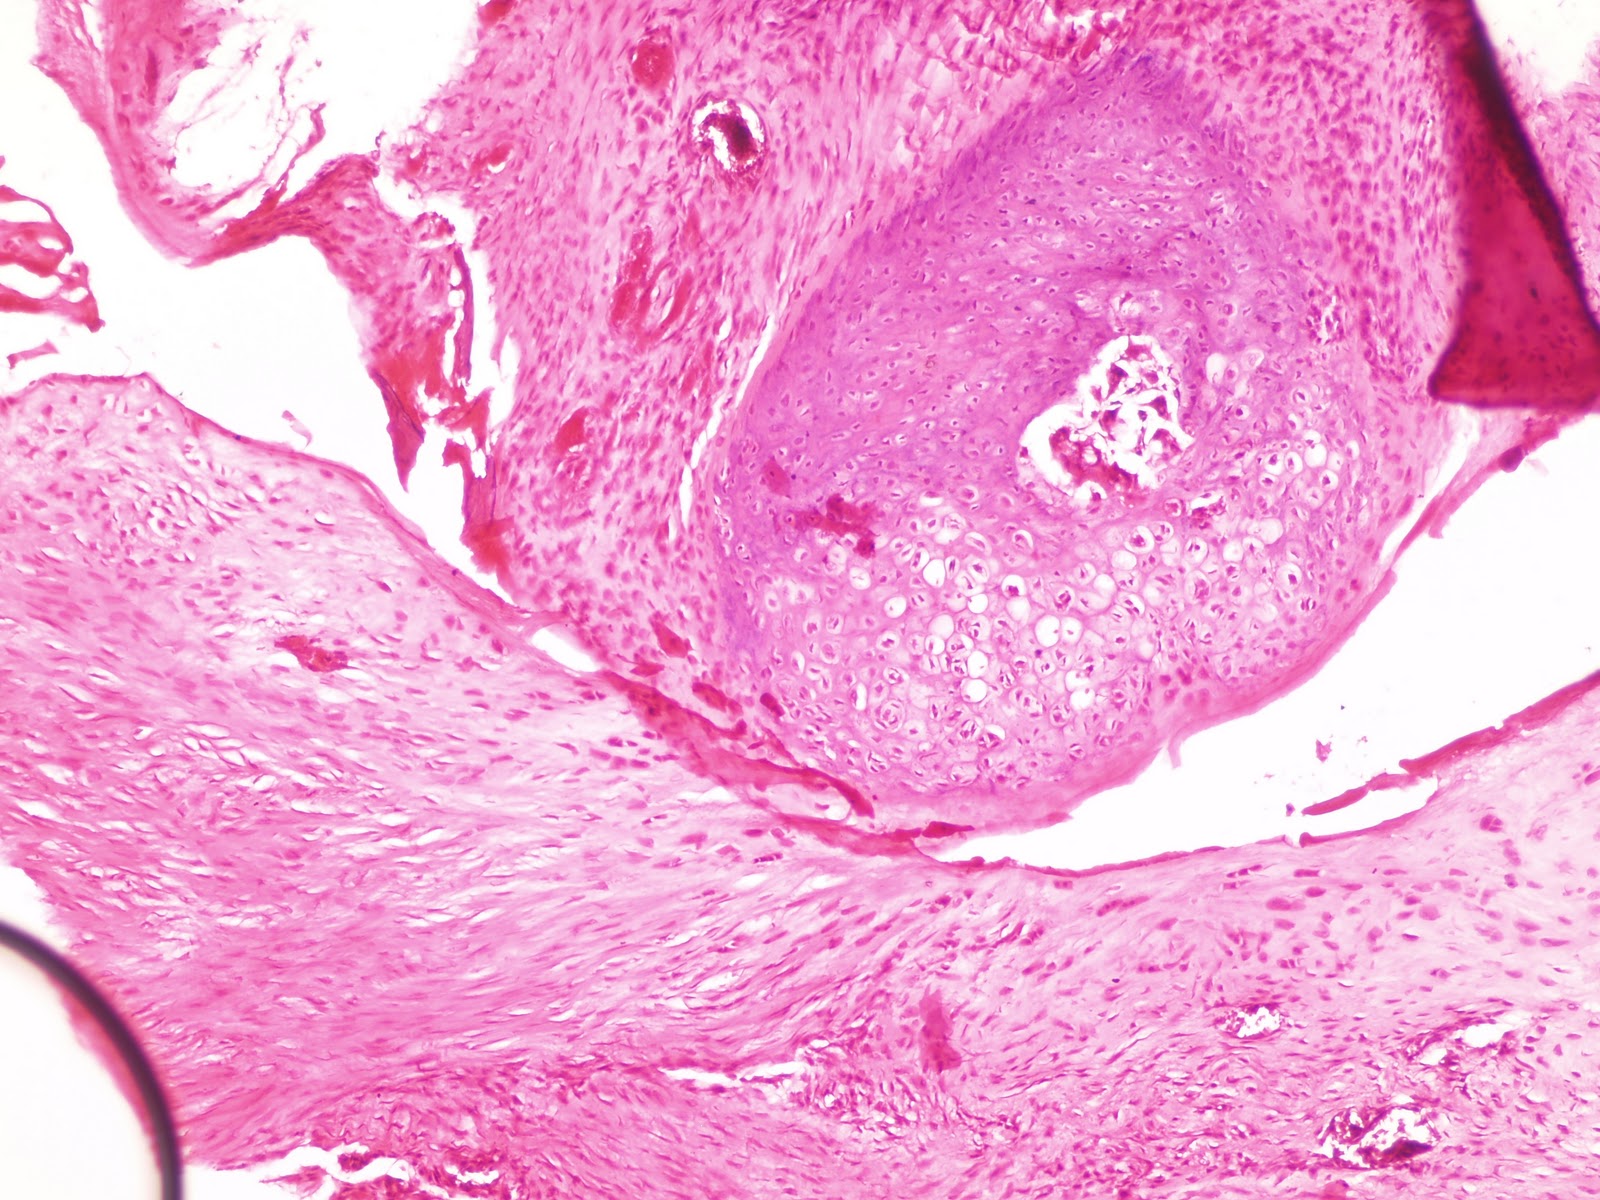

Corn Callus Histology . Corns and calluses at a glance; Corns are uncomfortable, thickened skin lesions that result from repeated mechanical trauma due to friction or pressure forces. Corns and calluses are thickened areas of skin due to repeated pressure, friction, or irritation. Corns demonstrate epidermal hyperplasia with a thick and compact stratum corneum. Corns and calluses result from prolonged application of forces to the skin and produce painful. There may be mucin deposition in the dermis, hemorrhage around blood vessels, streaking of collagen on the sides of the dermal papillae. Callus shows a markedly dense, usually orthokeratotic stratum corneum underlain by mild acathosis, variable hypergranulosis, and increased collagenization of the superficial dermis. Whereas calluses demonstrate only orthokeratosis,.

Pathology Outlines Histology Corn Callus Histology Callus shows a markedly dense, usually orthokeratotic stratum corneum underlain by mild acathosis, variable hypergranulosis, and increased collagenization of the superficial dermis. There may be mucin deposition in the dermis, hemorrhage around blood vessels, streaking of collagen on the sides of the dermal papillae. Corns demonstrate epidermal hyperplasia with a thick and compact stratum corneum. Whereas calluses demonstrate only orthokeratosis,.. Corn Callus Histology.